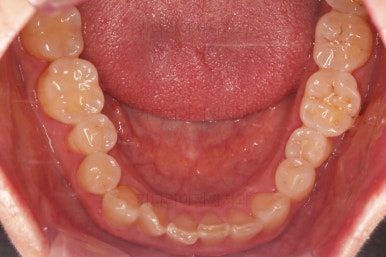

초진 때의 사진입니다.

전반적으로 치열이 삐뚤하고 불균일한 양상이긴 하지만 꼭 이런 부분들까지 교정을 해야 하는 건 아니에요.

해당 부분의 어금니가 1개가 없었어요.

어금니가 없어진지 꽤 시간이 흘렀기 때문에 몇 가지 문제점이 나타나는데요.

앞쪽 치열들도 발치된 자리로 조금씩 이동하는 바람에 틈새가 듬성듬성 생겼어요.